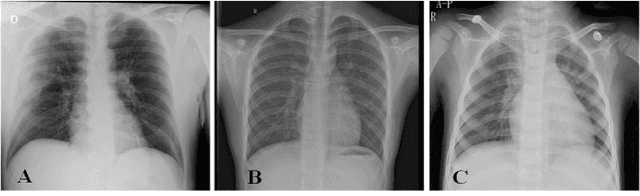

Abstract:The field of medical imaging is an essential aspect of the medical sciences, involving various forms of radiation to capture images of the internal tissues and organs of the body. These images provide vital information for clinical diagnosis, and in this chapter, we will explore the use of X-ray, MRI, and nuclear imaging in detecting severe illnesses. However, manual evaluation and storage of these images can be a challenging and time-consuming process. To address this issue, artificial intelligence (AI)-based techniques, particularly deep learning (DL), have become increasingly popular for systematic feature extraction and classification from imaging modalities, thereby aiding doctors in making rapid and accurate diagnoses. In this review study, we will focus on how AI-based approaches, particularly the use of Convolutional Neural Networks (CNN), can assist in disease detection through medical imaging technology. CNN is a commonly used approach for image analysis due to its ability to extract features from raw input images, and as such, will be the primary area of discussion in this study. Therefore, we have considered CNN as our discussion area in this study to diagnose ailments using medical imaging technology.